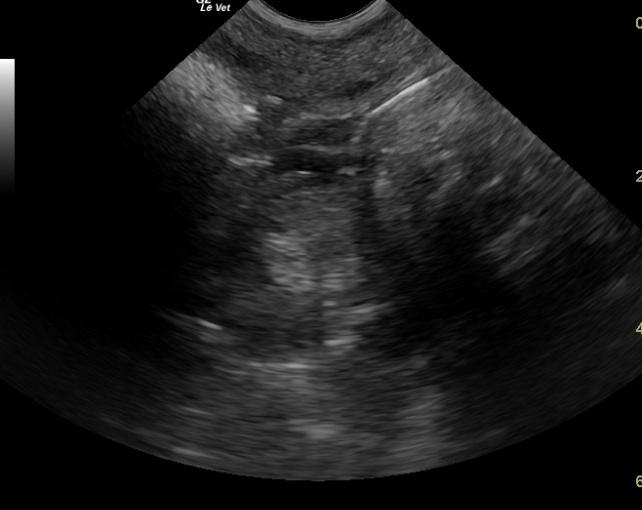

A 17 year old spayed female DSH cat was presented for constipation, dehydration and lethargy. Abnormalities on physical examination were dehydration and generalized DJD. On abdominal palpation, movable stool and possible splenomegaly was noted. Leukocytosis was present on CBC. Serum biochemistry revealed hypoalbuminemia and hyperamylasemia. T4 was normal, but free T4 was elevated.